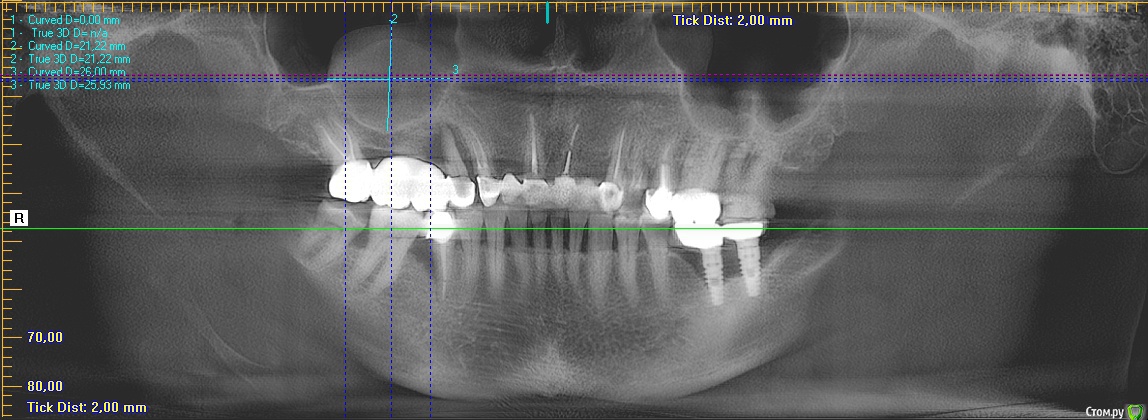

Nazim_NV86 Опубликовано 23 августа, 2018 Поделиться Опубликовано 23 августа, 2018 (изменено) Там в синусе было тоже самое что у вас на снимке. Левые два импланта изначально слишком коронально поставлены. Придётся вертикально ламину крепить. ЗДК на 45. На фоне этого убрать это образование из синуса кажется делом попроще. Изменено 23 августа, 2018 пользователем Nazim_NV86 Ссылка на комментарий